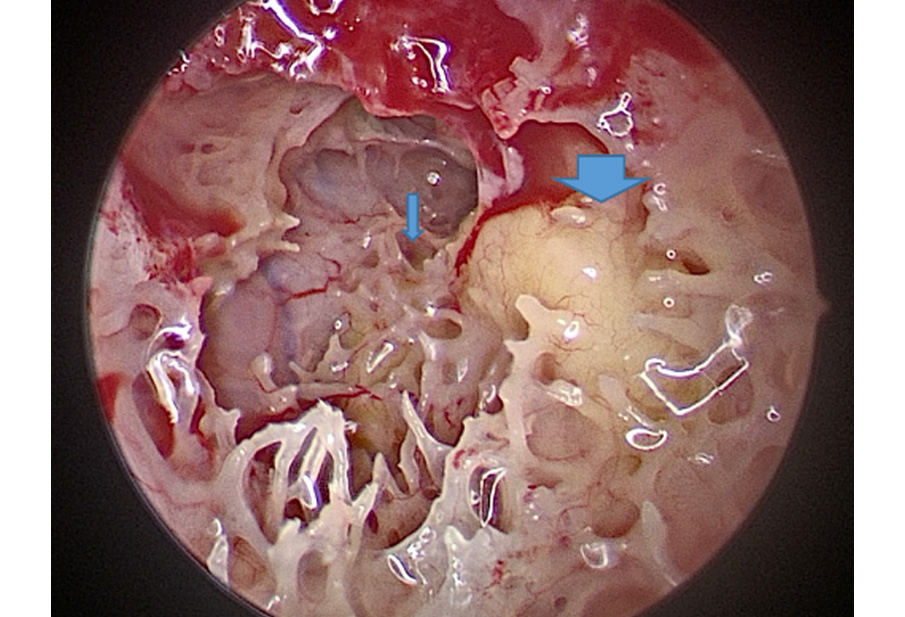

Orecchio destro.

Canale semicircolare laterale (Freccia grande). Canale semicircolare superiore (freccia piccola). (2022)

Bone pathè,

fatto di polvere di osso della persona

e colla biologica

Esposizione microchirurgica della meninge

della fossa cranica media

Posizionamento di bone pathè tra meninge e l’osso, fino a ricostruire in basso la parete deiscente del canale semicircolare superiore (freccia grande). Corpo dell’incudine (freccia piccola). Si mettono i punti retroauricolari, intervento finito entro due ore e a casa il giorno dopo.